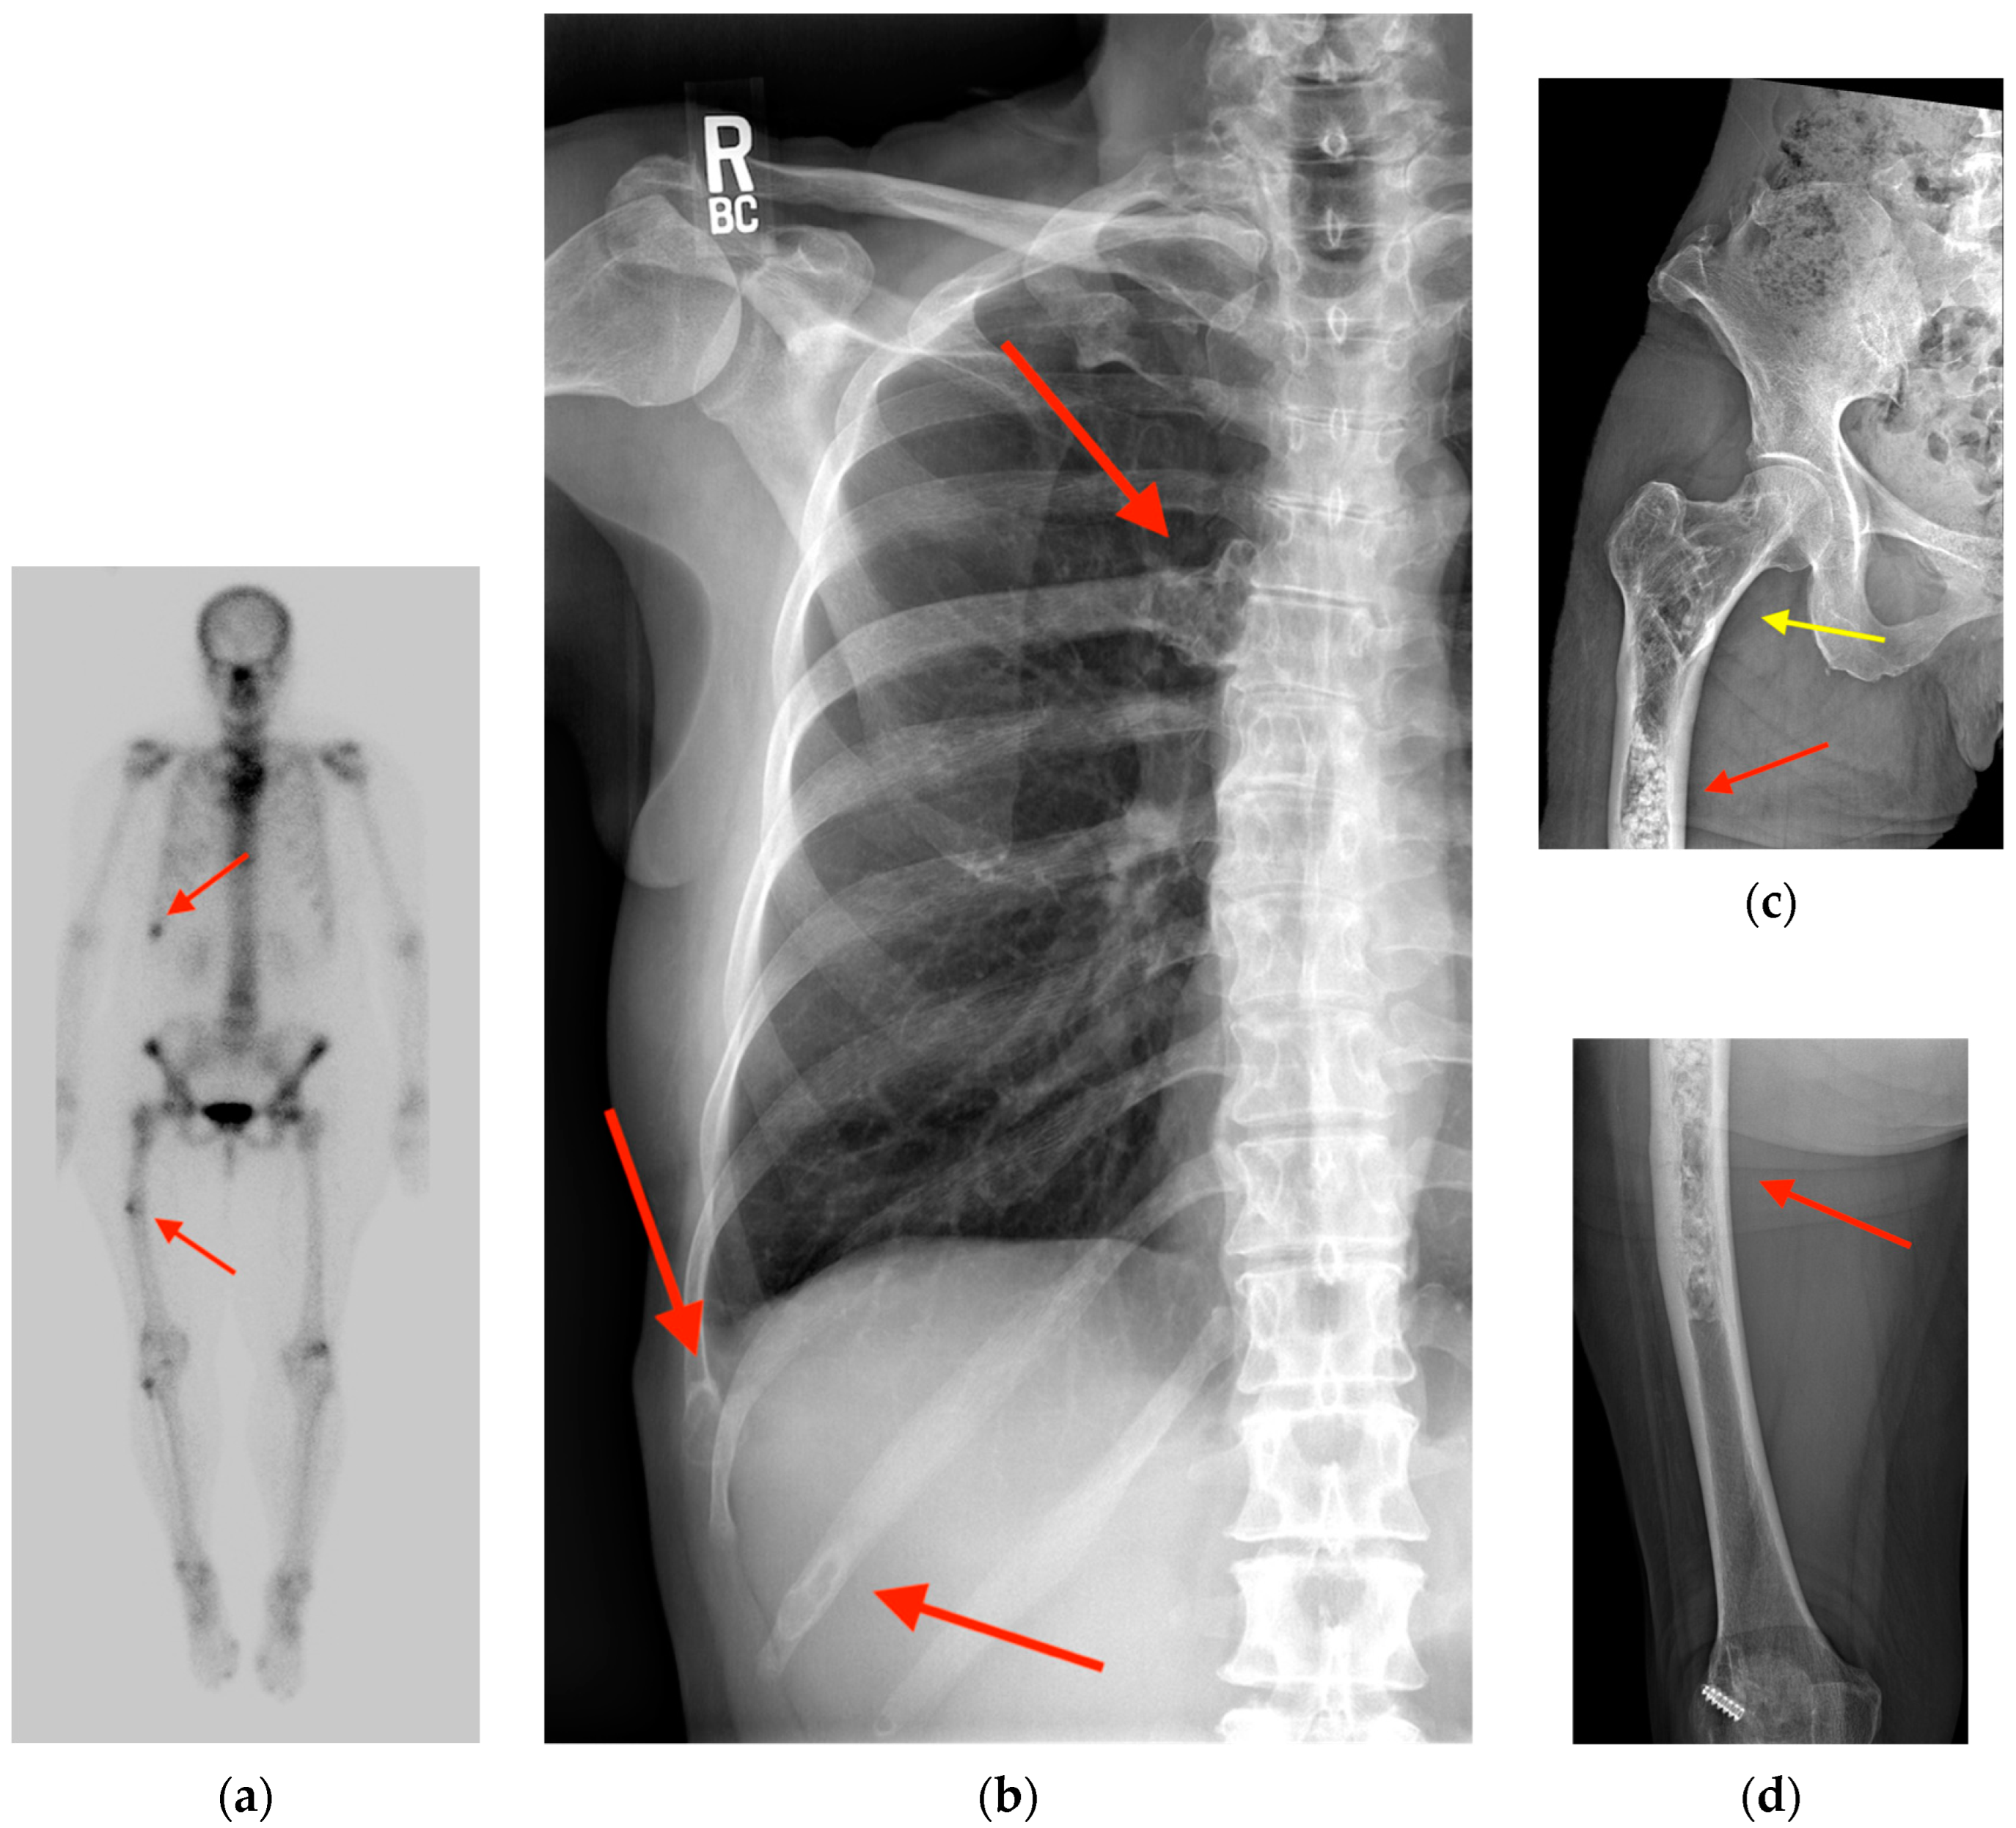

2.1. Fracture